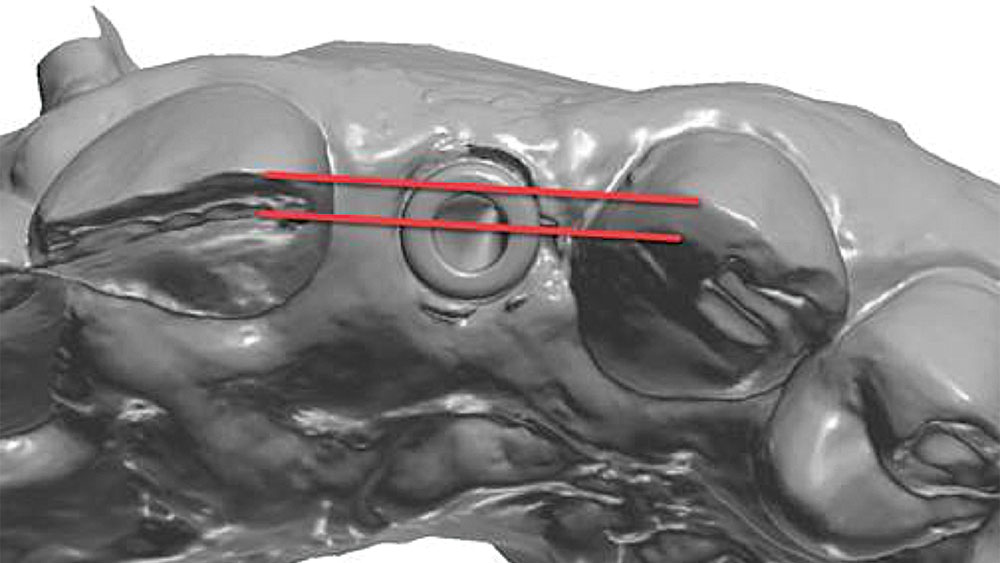

To achieve an optimal functional and esthetic outcome, the implant must be placed correctly with regard to trajectory, adjacent vital anatomy, and buccolingual, apicocoronal and mesial-distal positioning. Situating the implant so that the edges of the osteotomy are at least 2 mm from the buccal and lingual cortical plates, 2 mm from adjacent roots, 2 mm from vital structures, and 2–3 mm below the crest of tissue will keep the implant within the envelope of acceptability. The implant trajectory should emerge lingual to the incisal edge of the planned restoration, which allows for a screw-retained crown.

This case is an example of an ideal clinical situation for dentists who are new to placing implants in the esthetic zone. The patient requested treatment for a fractured upper lateral incisor. After extraction, grafting and healing, ample bone and soft tissue were present, and an implant was placed in optimal position for an esthetic result. The screw-retained restoration predictably restored form and function, illustrating the beautiful results that can be achieved by observing simple surgical and prosthetic guidelines.